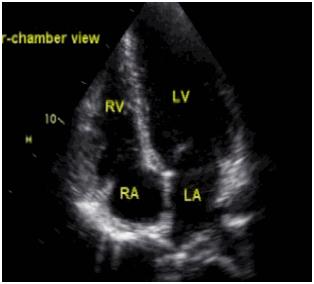

1.心脏彩超是什么

心脏彩超是一个能动态显示心腔结构、心脏搏动和心脏内外血液流动以及心脏周围毗邻结构的仪器。

其原理是通过心脏彩超探头,把探头下的组织结构显示在屏幕上的一种检查方法。

通俗的讲,心脏探头就像摄像机的镜头,随着“镜头”的转动,心脏的结构就会被显示在彩超屏幕上,从而给医生提供建议的一种检查方法。